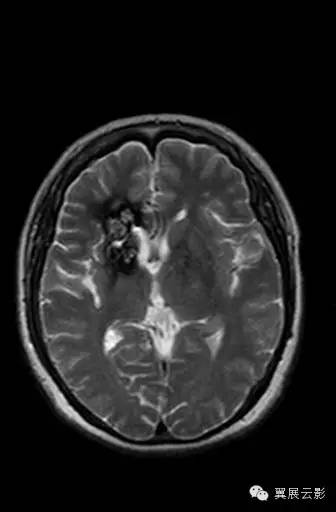

右侧基底节区可见不规则团片状混杂信号灶,累及右侧侧脑室前角,大小约15×34mm,边界尚清,呈爆米花样改变,T1WI等高信号,T2WI/FLAIR呈混杂稍高信号,边缘可见低信号环,无明显占位效应,DWI低信号。